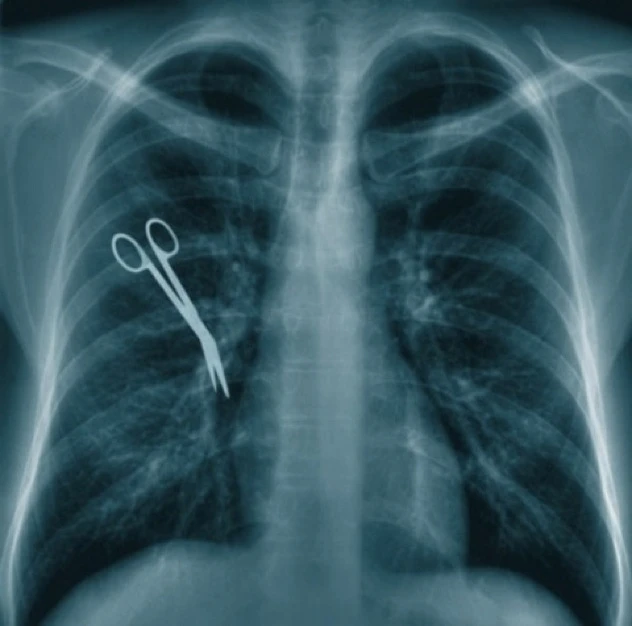

Năm 2008, chị Veronika Cruz được phẫu thuật cắt một bên buồng trứng ở một cơ sở y tế tại Sao Paulo, Brazil. Bác sĩ kíp mổ đã để quên chiếc kéo dài hơn 20 cm trong bụng chị đến 3 năm sau mới được phát hiện, khiến người phụ nữ 35 tuổi này luôn cảm thấy đau đớn. Tuy nhiên, khi chị đến gặp và phàn nàn với những người từng mổ cho mình thì họ gạt đi. Chỉ đến khi chị Veronika suy sụp và phải vào viện chụp X-quang, sự thật mới được sáng tỏ.